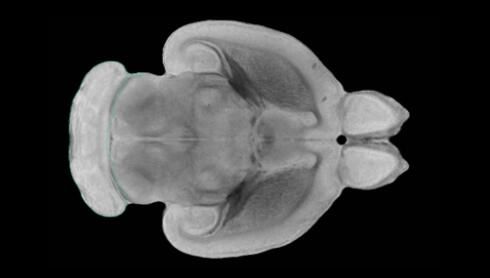

近日,一項刊登在國際雜志Nature上的研究報告中,來自劍橋大學的科學家們通過研究揭示了隨著年齡增長大腦僵硬程度的增加導致大腦干細胞功能異常的分子機制,同時研究者還開發(fā)出了一種新方法能將老化的干細胞逆轉回年齡健康狀態(tài);相關研究結果有望幫助研究人員理解機體大腦的老化過程以及如何開發(fā)治療年齡相關大腦疾病的新型療法。

隨著機體年齡增加,肌肉和關節(jié)都會變得僵硬,這就會使得日常活動變得更加困難,本文研究表明,我們的大腦也是如此,與年齡相關的大腦僵硬對大腦干細胞的功能或許有著重要影響。文章中,研究人員對年輕和老化大鼠的大腦進行研究闡明了年齡相關大腦僵硬對少突膠質(zhì)前體細胞(OPCs,oligodendrocyte progenitor cells)功能的影響。OPCs是一類對維持正常大腦功能非常重要的大腦干細胞,其對于髓磷脂的再生也非常重要,髓磷脂是神經(jīng)組織周圍的脂肪鞘,在多發(fā)性硬化癥中髓磷脂的再生常常會被損傷,機體老化對這些細胞的影響常常會誘發(fā)多發(fā)性硬化癥的發(fā)生,這些細胞的功能在老化的健康人群中同樣會下降。

為了確定老化OPCs的功能缺失是否可以被逆轉,研究人員將來自老化大鼠機體的老化OPCs轉移到了年輕大鼠柔軟的海綿狀大腦組織中去,值得注意的是,這些老化的大腦細胞能夠重新恢復活力,其行為非常像年輕更加強壯的細胞。這項研究中,研究人員在實驗室中開發(fā)出了具有可變僵硬程度的新型材料,并在受控環(huán)境下研究這些材料的生長及其對大鼠大腦干細胞的影響,這些材料能被工程化改造具有和年齡或老化大腦相似的柔軟程度。